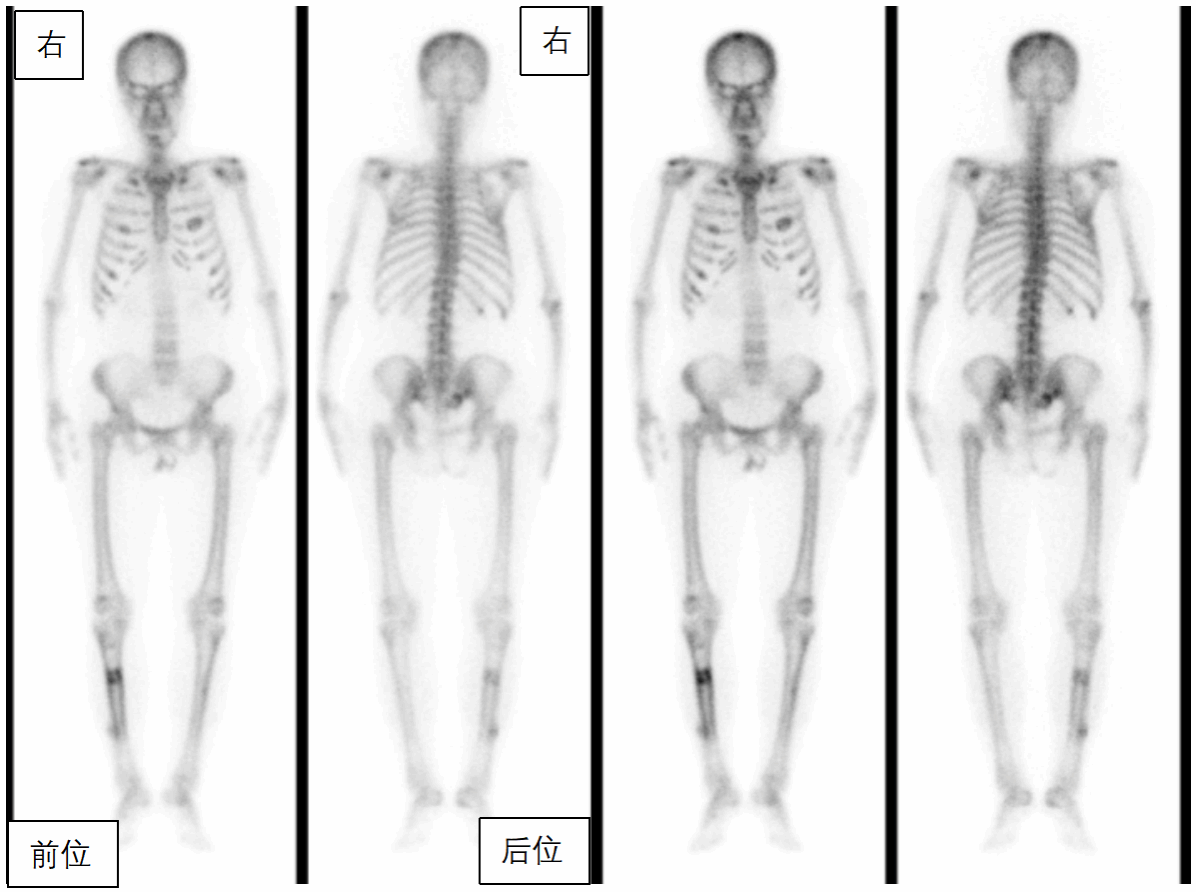

段阿姨,59岁,因腰背部疼痛1月,外院查CT示肋骨、骶骨骨质异常,骨转移?遂来核医学科行全身骨显像,判断是否是骨转移,图像(图1)如下:

全身骨骼显像剂分布弥漫性增强,肩胛骨、双侧部分肋骨、骶骨、右胫骨存在灶性显像剂异常浓聚,双肾及软组织本底显示不清,呈“超级骨显像”。

全身骨显像不仅能显示骨骼的形态,同时能反映骨骼和病变的局部血流及代谢情况,具有灵敏度高、观察范围广的特点,通过对全身骨骼代谢异常的分布特点来诊断一些代谢性疾病、系统性疾病,比如原发性甲状旁腺功能亢进症所引起的代谢性骨病,除表现为超级骨显像外,还可以表现为“黑颅征”(图7)、“串珠肋”、“领带征”等典型的征象。